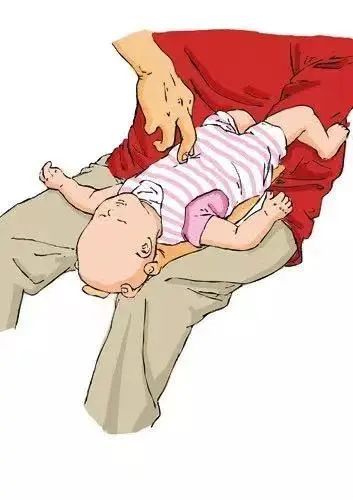

对于1岁以下婴幼儿,一只手托其面颊,使其面部朝下,头低于臀位,另一只手掌根部拍打其背部中央(两肩胛骨连线中点)5次,观察有无异物排出。若无异物排出,可让宝宝翻转使其面部朝上,一手固定宝宝,另一只手食指和中指按压孩子两乳头连线中点部位5次,观察有无异物排出。